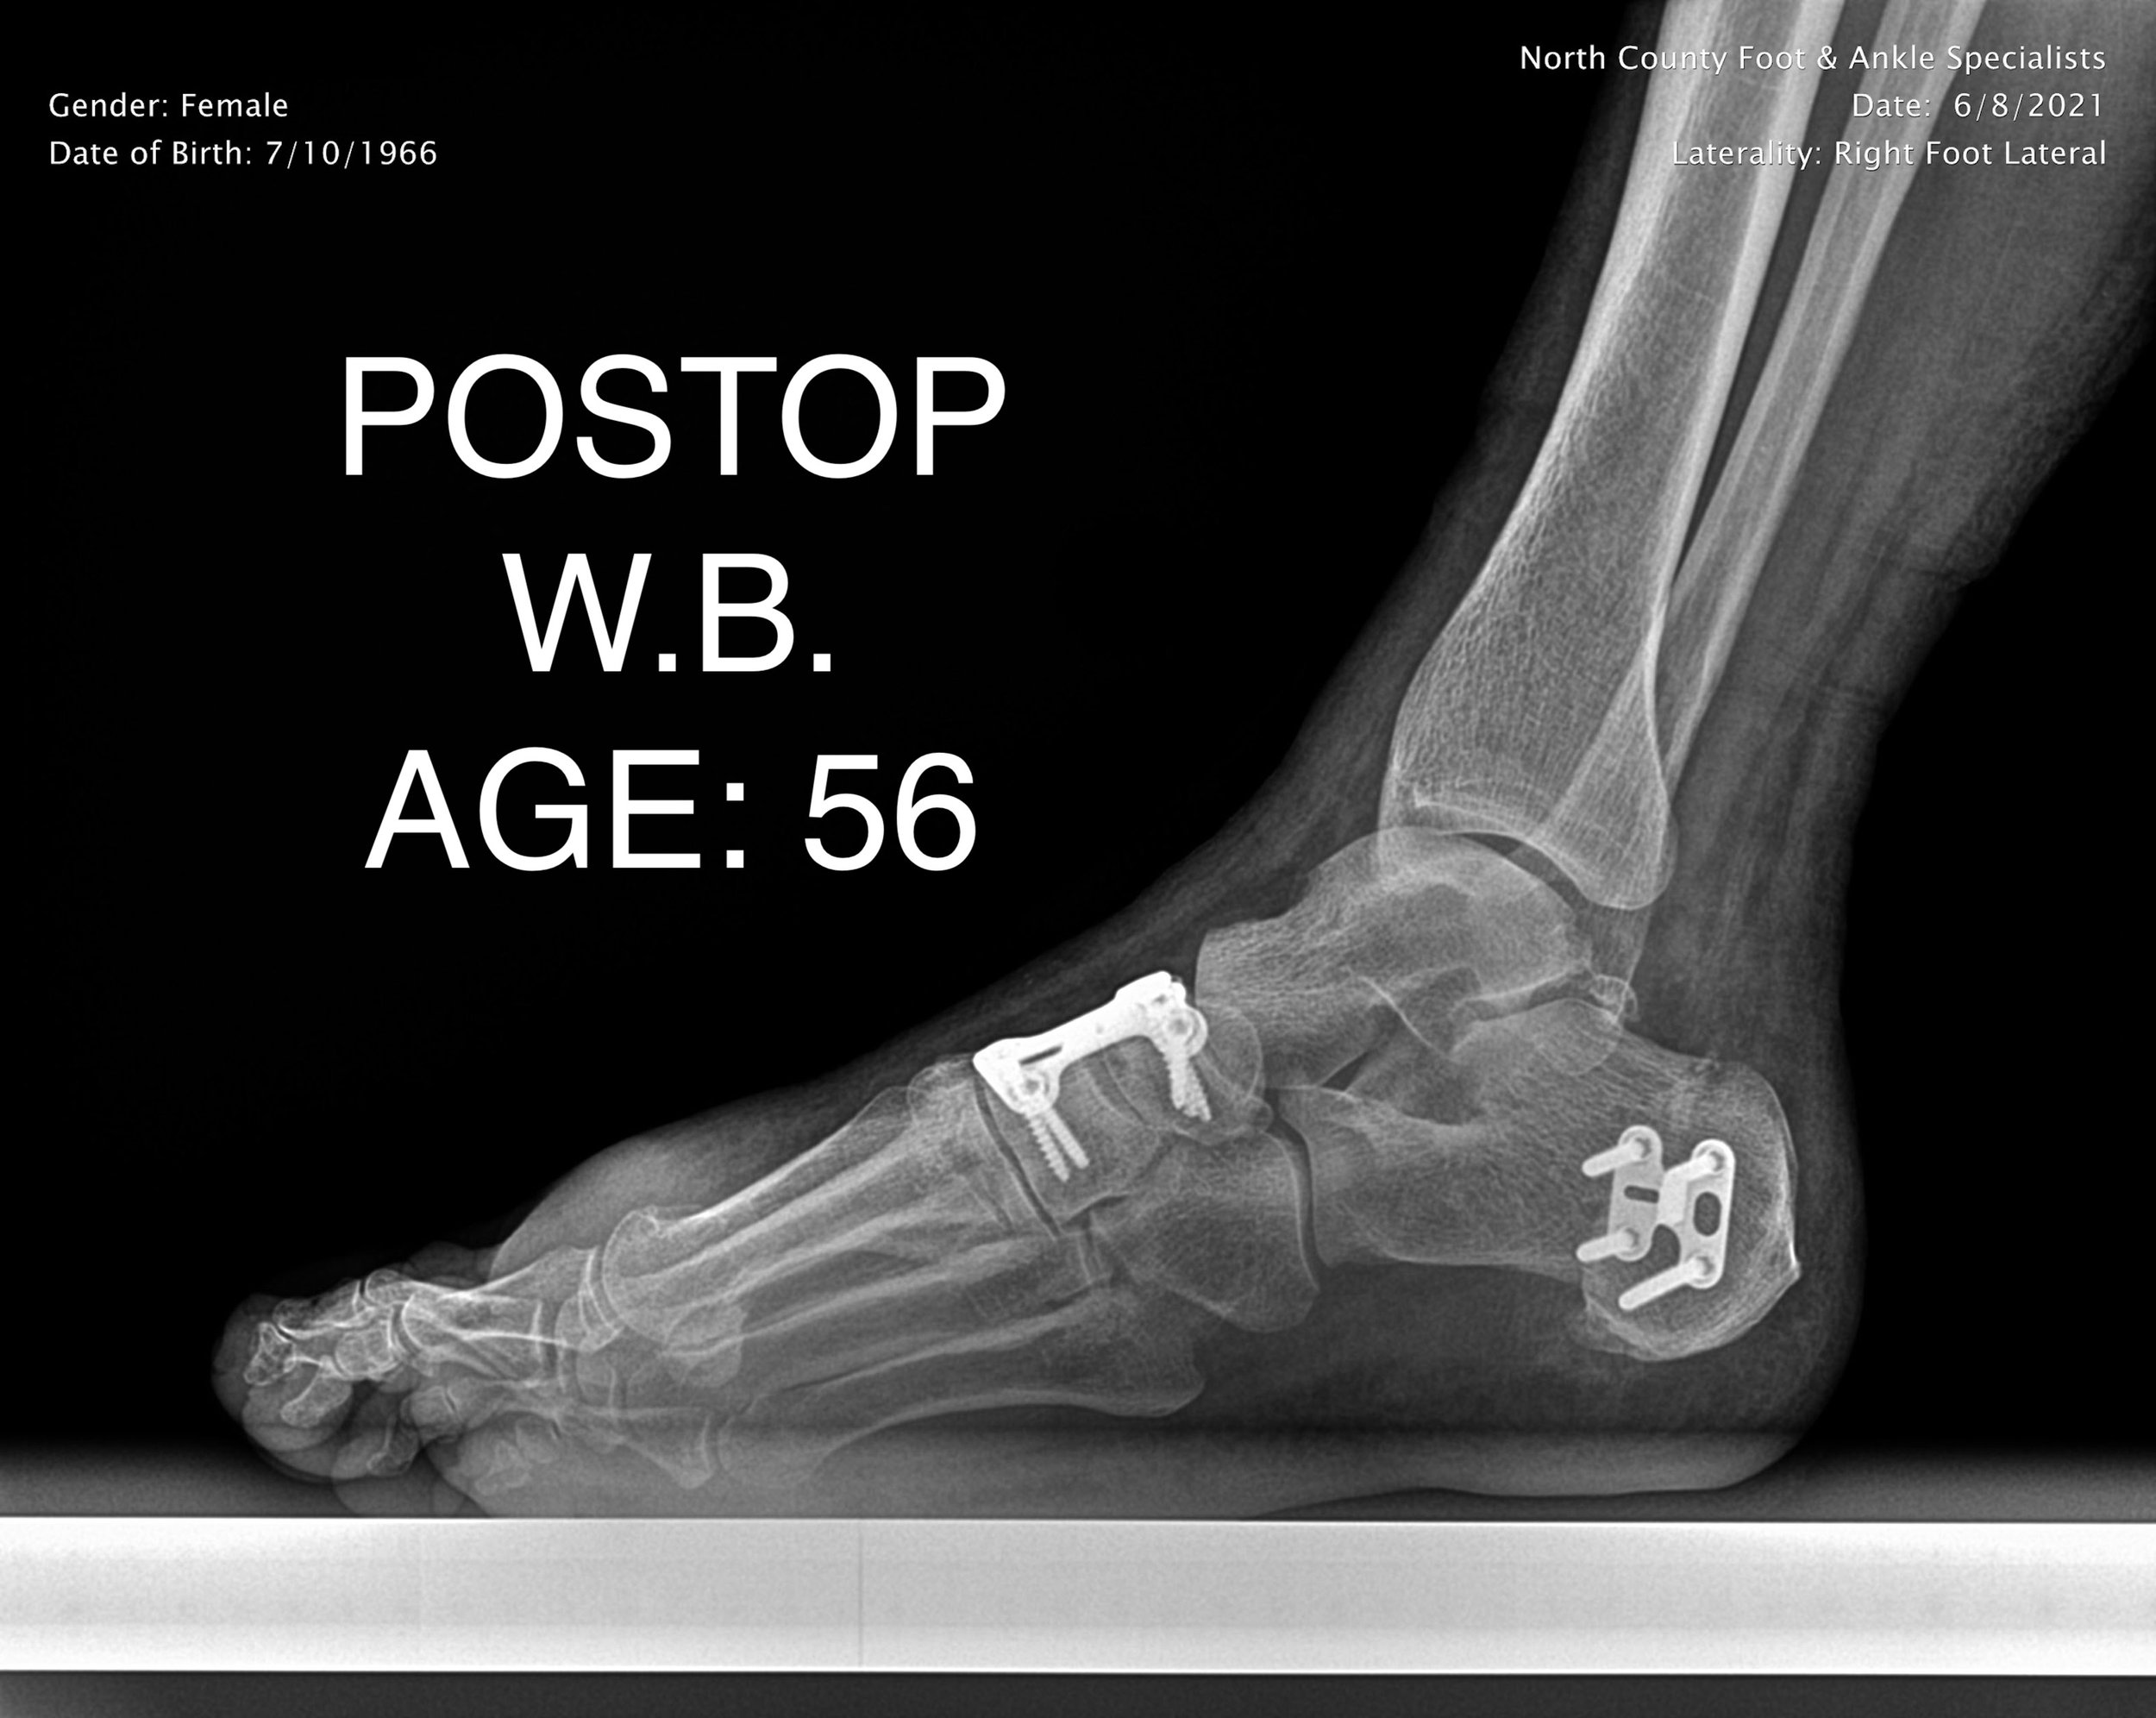

REAR FOOT FUSION